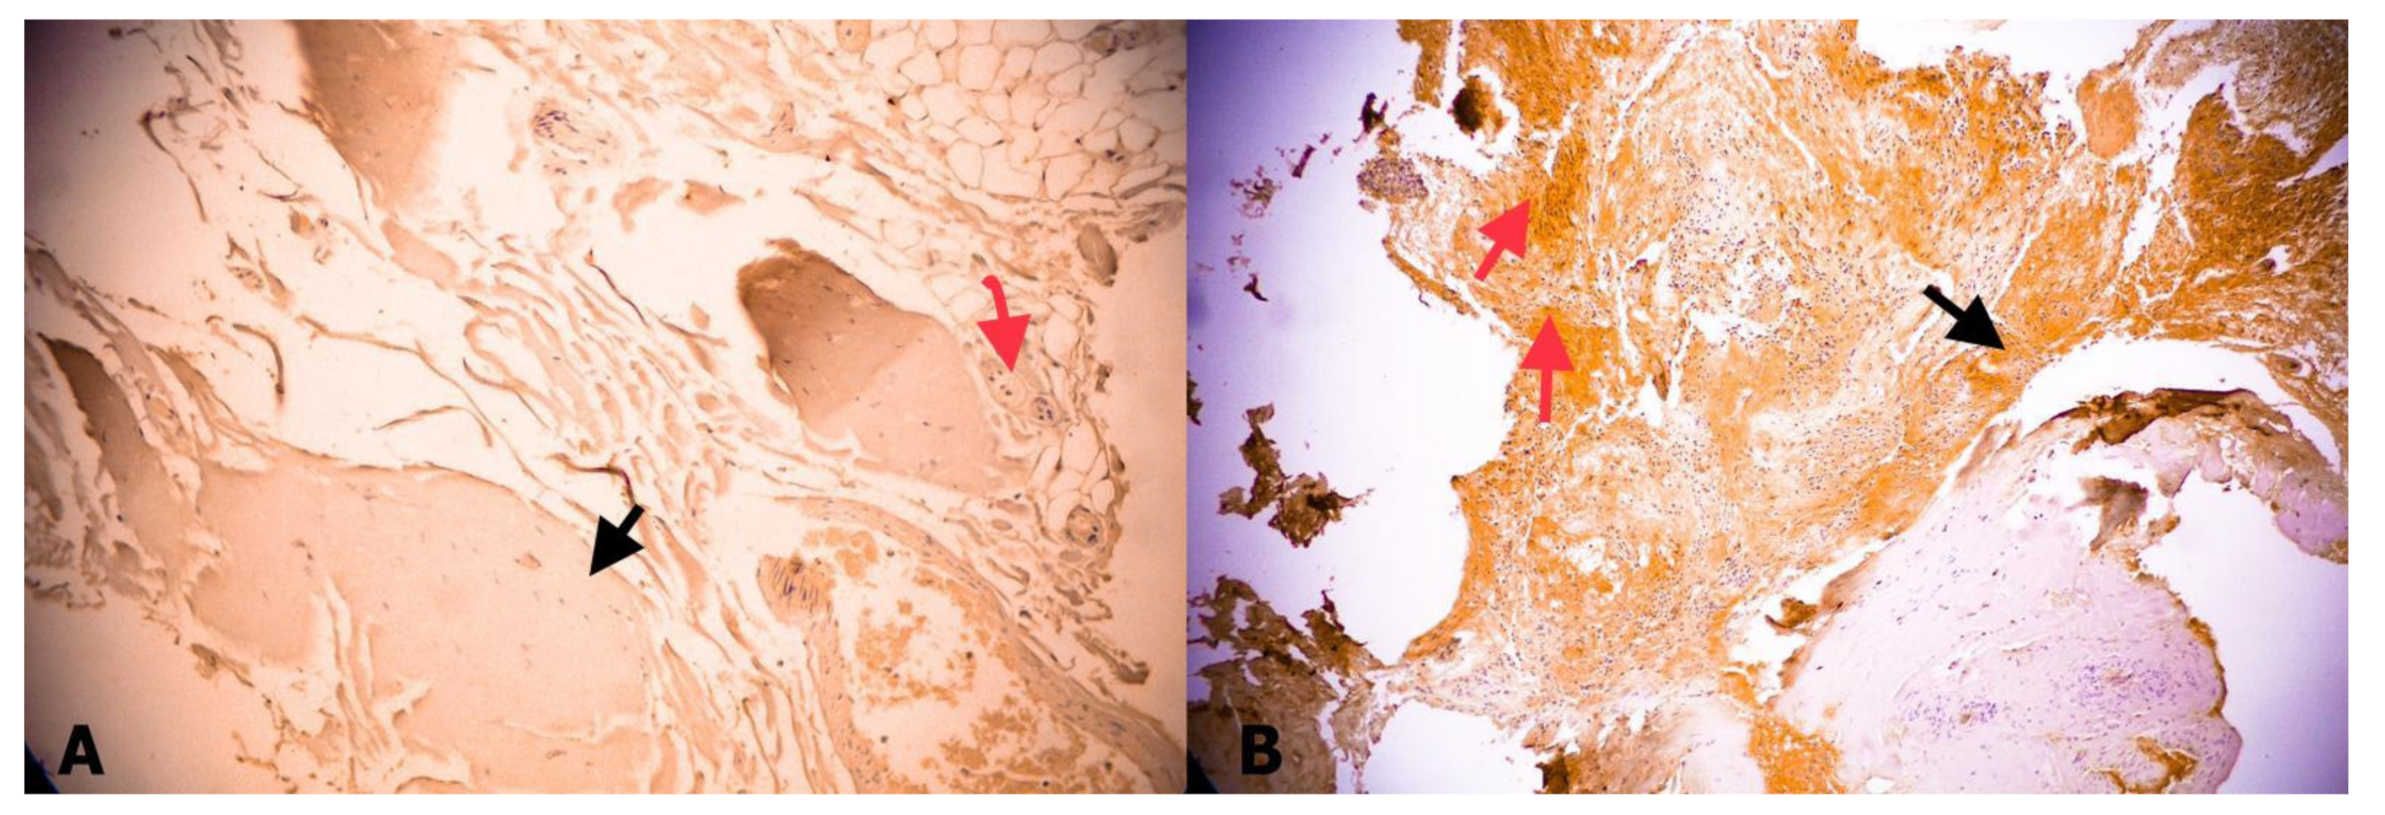

However, it was mostly negative or weak in Group 2. In addition, connective tissue and ganglion cells were obvious in Group 2 (Figure 4). Weak expression sigma-class GST was observed in 6 (40%) of 15 Group 2 samples (Table 2). This expression was also mostly weak in Group 1, but frequent, in 8 (80%) of 10 samples. Although sigma-class GST expression was higher in Group 1, the difference was not statistically significant (p = 0.197) (Figure 5).

Figure 5.

(A) No expression of sigma-GST in a fetal FT; black arrow indicates collagen, red arrow indicates neural tissue (GST, ×40). (B) Moderate expression of sigma-GST in FT of patient with TCS. Black arrow indicates collagen, red arrow indicates neural tissue (GST, ×40).